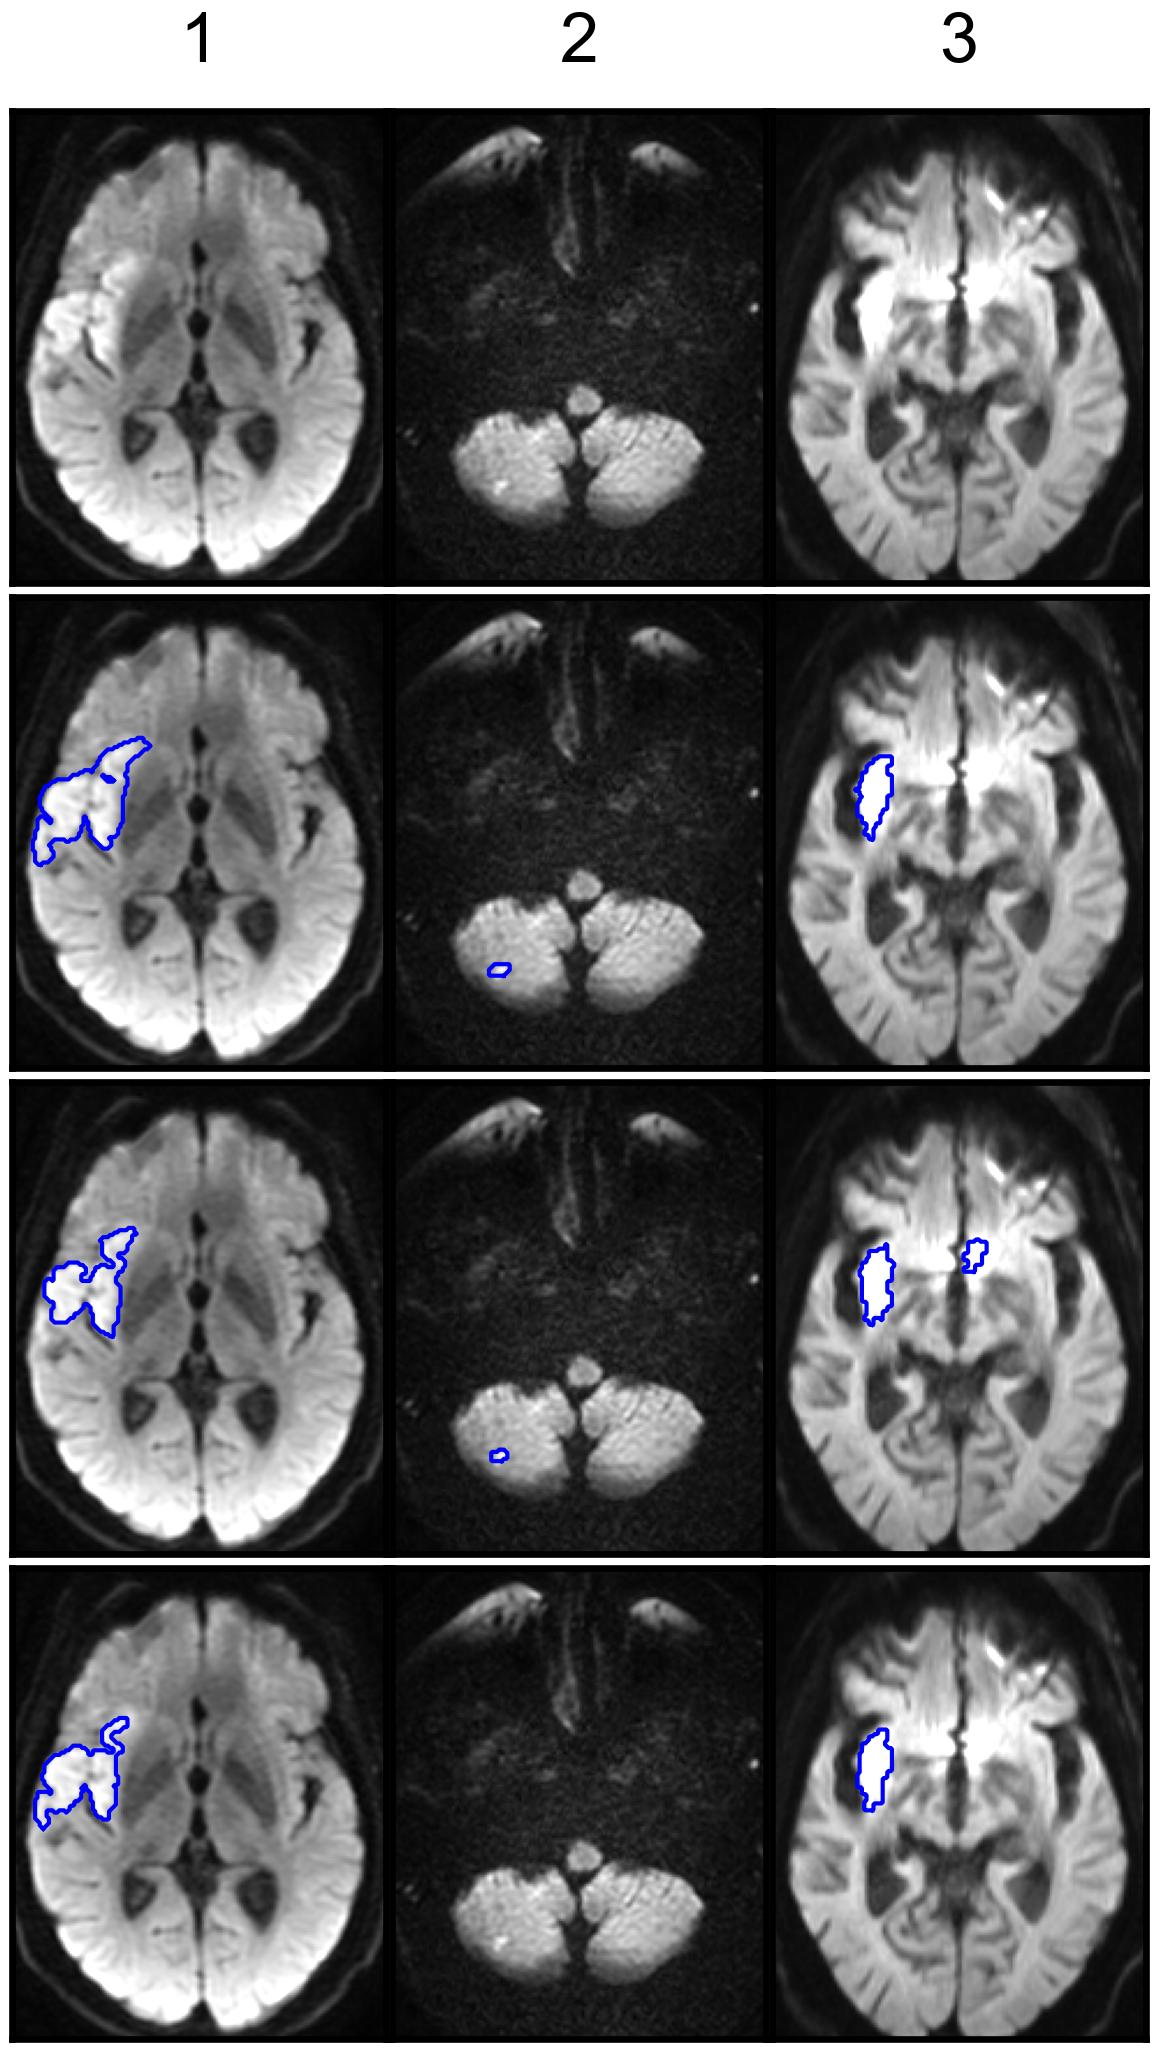

We conducted qualitative comparisons between the best-performing SOTA and ISLA models.

First, within each lesion-size group, we selected for visualization axial slices from the volumes closest to the first, second, and third quartiles of the DSC difference between the two models, excluding cases whose DSC deviated by more than 0.2 from the respective model-specific median within the group.

Figure 4 shows representative examples of segmentations from the test set with DAGMNet and ISLA-ENS, the best SOTA and ISLA models according to the test set case-level ranking (Table 5).

In cases 1 and 2 of Figure 4(a), both models successfully detected the lesions; however, DAGMNet slightly underestimated the lesion extent in case 1. In case 3, a corticospinal tract anisotropy artifact resulted in FPs for DAGMNet.

Cases 1 and 3 of Figure 4(b) further illustrate underestimation of lesion extent by DAGMNet, whereas ISLA-ENS produced segmentations closely matching the manual annotations. In case 2, both models generated FPs due to magnetic-susceptibility artifacts near the nasal region.

In Figure 4(c), case 1 shows accurate delineation of the lesion by both models, with no FPs induced by the inhomogeneity artifact. Case 2 demonstrates a missed small cerebellar lesion by ISLA-ENS. In case 3, both models correctly localized the lesion, but DAGMNet again produced FPs caused by magnetic-susceptibility artifacts around the nose.